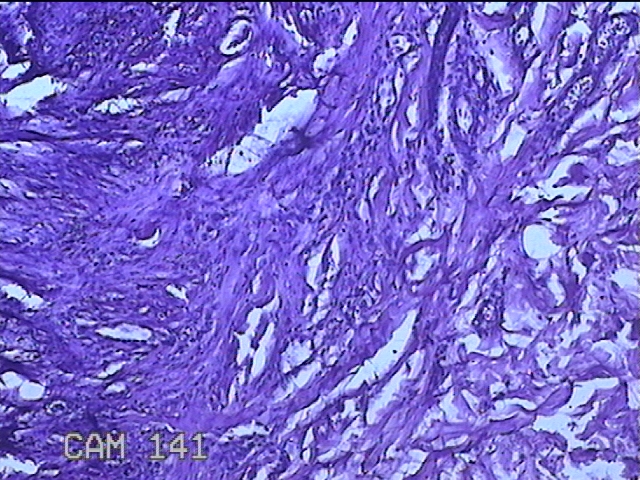

左侧臀部结节

性别

男

年龄

40岁

临床诊断

皮下结节

一般病史

发现左侧臀部结节1年余。

标本名称

大体所见

灰白粉红色组织1.3x0.8x0.3cm一块,表面带梭形皮肤1.3x0.8cm,皮下见结节1.3x1x0.7cm一个,切开结节呈实性,切面灰白粉红色,质软。